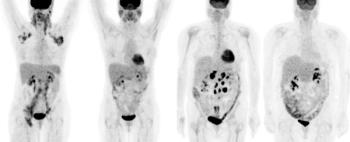

Cancer survivors and others with chronic conditions, backed by patient advocacy groups, gathered on Capitol Hill in Washington, DC, Wednesday to protest proposed imaging services reimbursement cuts they fear will reduce access to essential diagnostic imaging services, particularly in rural communities.